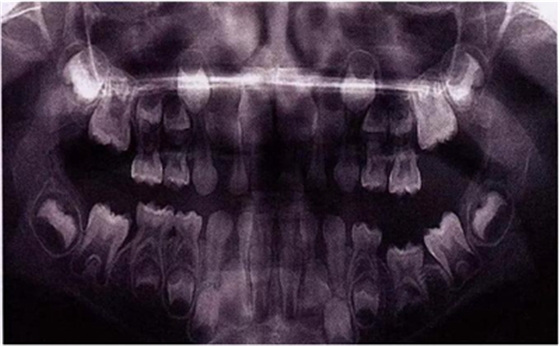

X線片還會(huì)顯示合平面呈現(xiàn)出一個(gè)臺(tái)階,并通常會(huì)有一個(gè)角度朝向固連牙的角型牙槽骨缺損。(圖5)。許多臨床醫(yī)生更愿意選擇拍攝曲面體層片而不是根尖片,因?yàn)榭紤]到乳牙下沉經(jīng)常會(huì)雙側(cè)發(fā)生并合并其它發(fā)育異常,同時(shí)也為了確定是否需要正畸治療。臨床檢查和影像學(xué)檢查聯(lián)合評(píng)估同樣也為了排除其它病因,譬如原發(fā)性的萌出障礙,牙齒嵌入或者其它異常。

圖9:一名五歲患兒右側(cè)下頜第二乳磨牙嚴(yán)重下沉的曲面體層片

圖11是一張曲面體層片,上面顯示了一名九歲男孩同時(shí)患有55,75,和85的下沉。其55和85 為中度下沉,75為輕度下沉。這幾顆牙都沒(méi)有齲齒,都伴有恒牙胚的存在,并且沒(méi)有鄰牙傾斜和間隙喪失的臨床表現(xiàn)。給予這個(gè)孩子的方案是醫(yī)囑三個(gè)月常規(guī)復(fù)診以觀察監(jiān)測(cè)這些牙的下沉情況。結(jié)果這些牙均未加重至超過(guò)中度下沉,并且全部自然脫落,恒牙正常萌出。

圖11:曲面體層片顯示一名9歲男孩乳磨牙下沉,繼承恒牙胚存在。